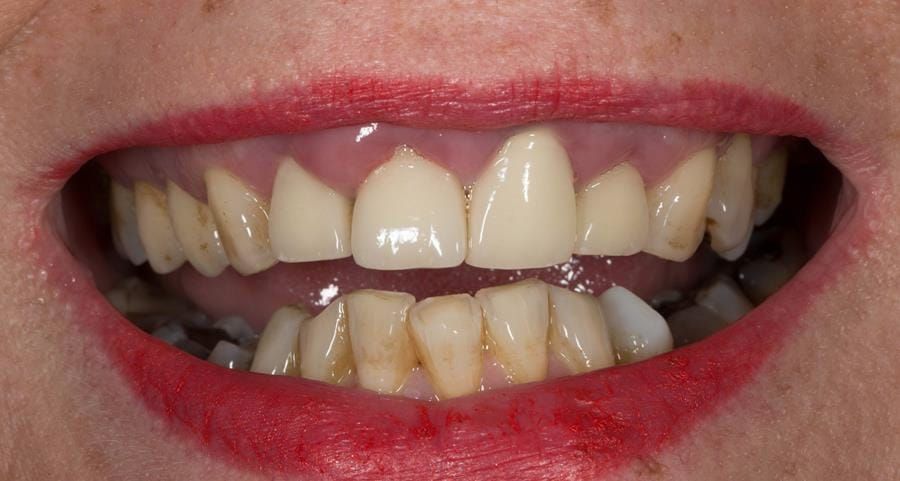

- High smile line showing gum above gingival zeniths of upper front teeth when smiling. Aesthetic failure of the upper four incisors with inflammation of the gingivae and mis-match of the gingival zenith levels.

- Other than the maxillary incisors the remaining dentition was in marginally better condition being moderately to heavily restored. Many will probably require replacement and restoration from time to time mainly from wear and tear owing to occlusal forces.